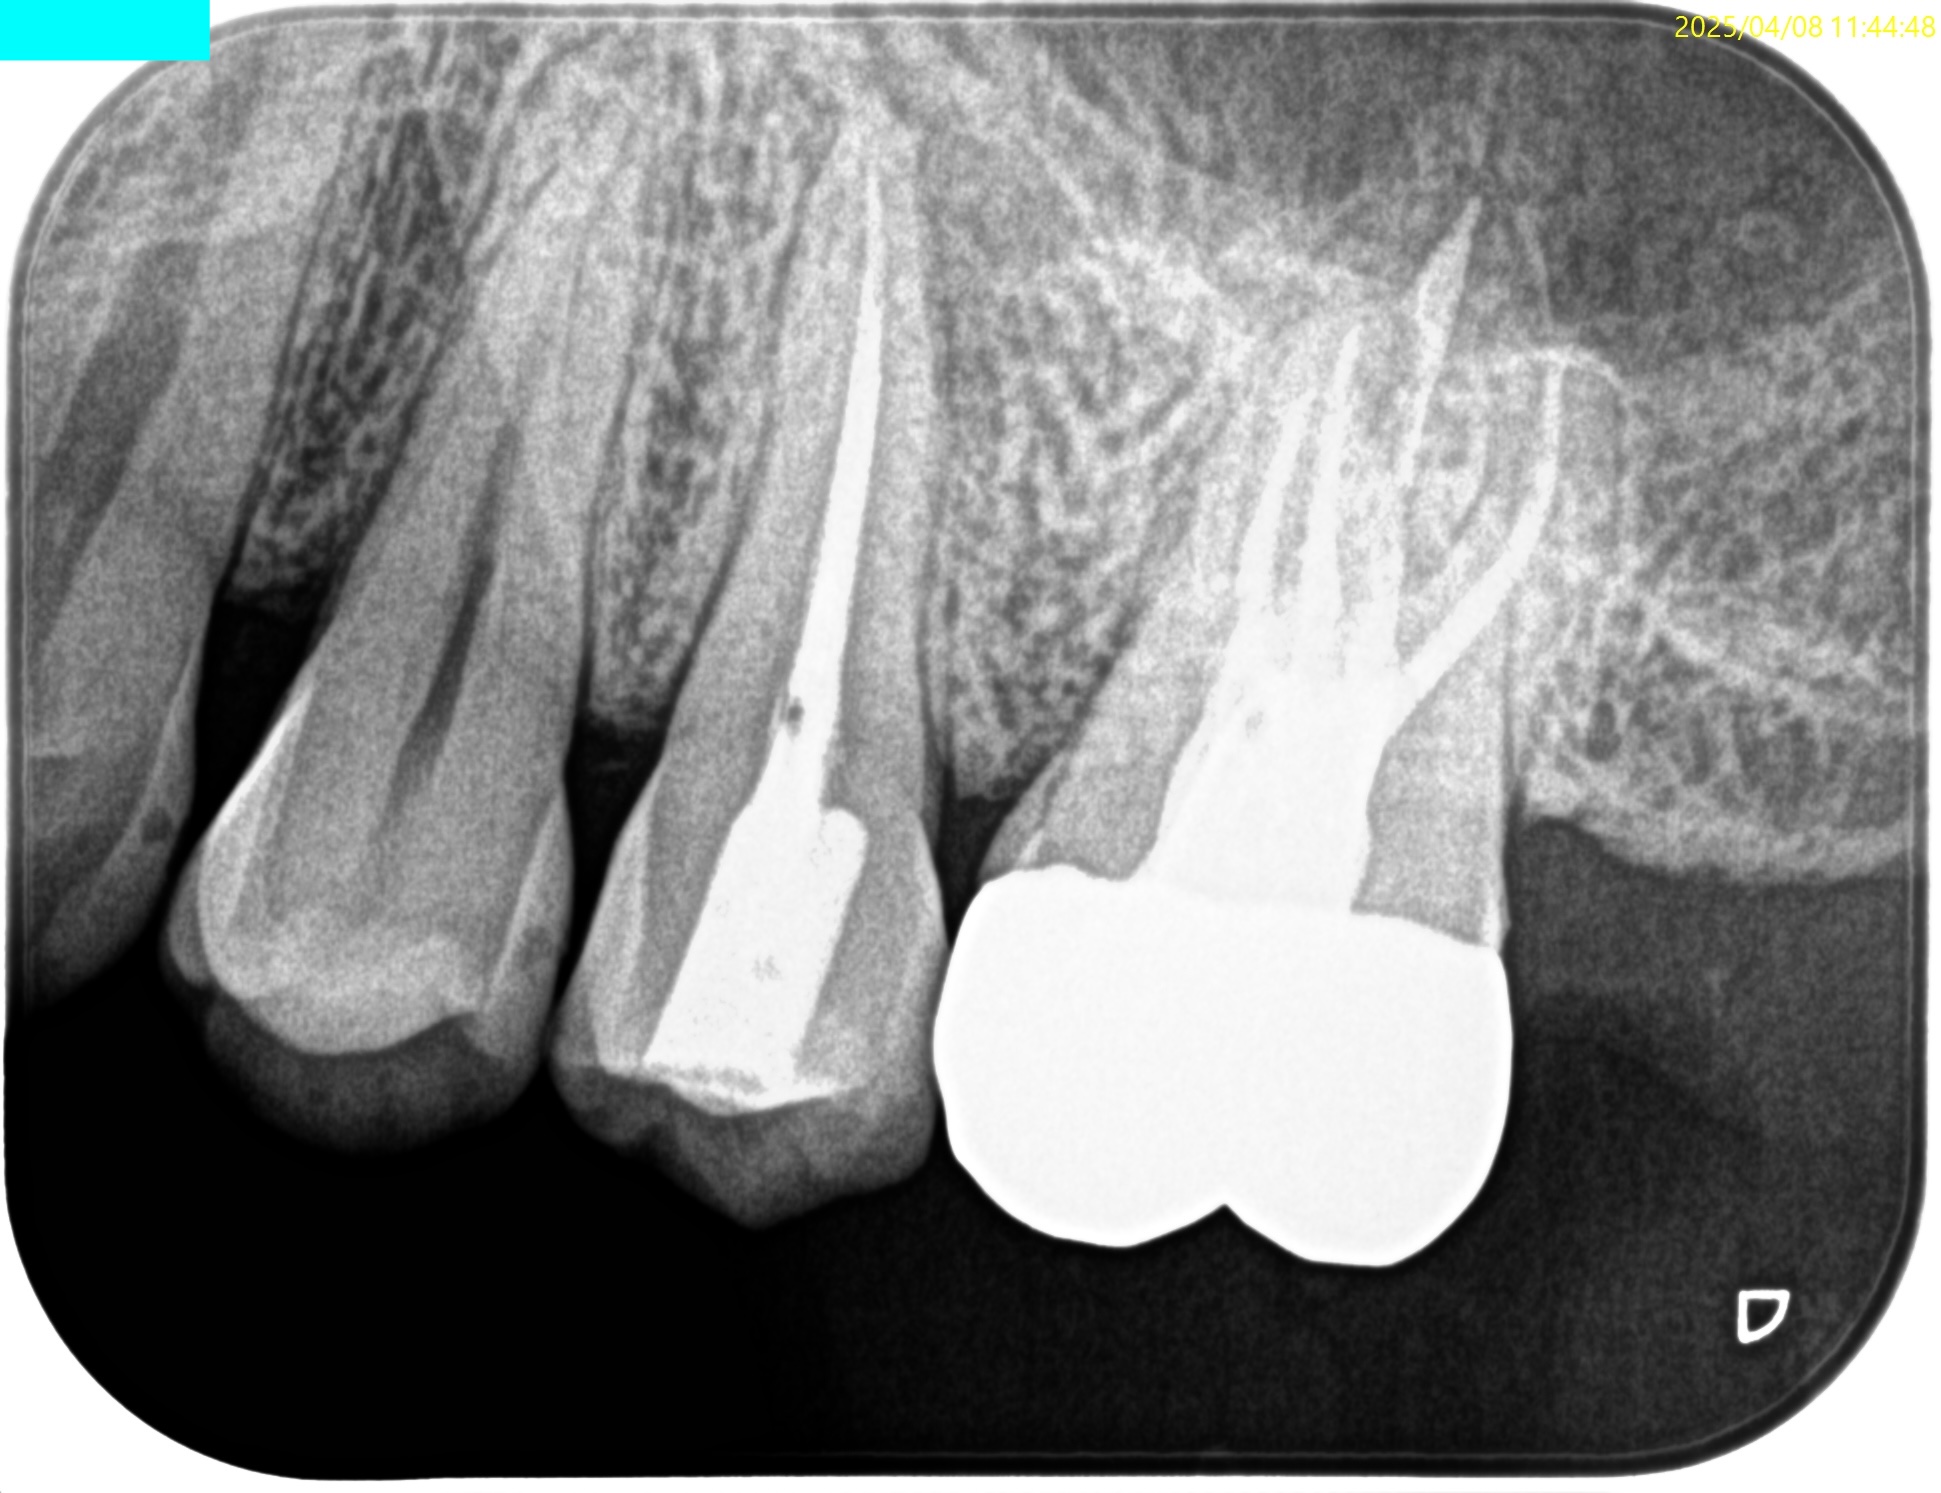

#13,14 RCT 2yr Recall(2025.4.8)

#13に咬合痛がある。

#13の根尖部に病変が見える。

#13

主根管に設定したB根管の根尖部の遠心側に根尖病変がある。